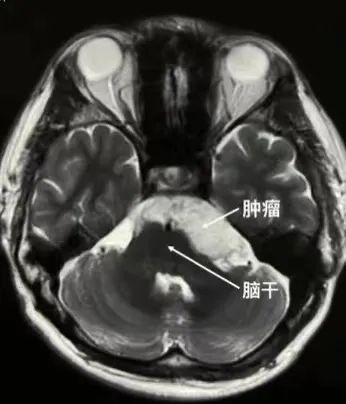

医生告诉他头痛的原因是脑内长东西了——颅内胆脂瘤(珍珠瘤)。虽然临床上,大多数表皮样囊肿是良性病变,但通过头颅磁共振检查发现,在陈先生桥脑小脑角区、桥前池、环池的肿瘤长约6cm,局部脑干及小脑明显受压,如不能及时解除压迫,随着肿瘤不断增长,将会对周围神经系统形成不可逆性损伤,遗留持久性功能障碍。

在十余年的生长过程中,几乎所有的神经和血管间隙里都长满了肿瘤,这时就要非常仔细地从各个角度将肿瘤分块切除,肿瘤位于脑干的前方,稍有不慎,就有可能导致呼吸心跳的改变,肿瘤因为生长较大,有一部分肿瘤从左侧跨过中线长到了右侧,导致一部分肿瘤“死角”无法使用显微镜观察到,这是神经内镜就派上了用场,从已有的手术通道置入内镜系统,在内镜下,所有藏在死角的肿瘤也无处可逃,都被一点一点地移除。电生理监测提示各支颅神经功能完好。经过3个多小时紧张手术终于顺利切除肿瘤。